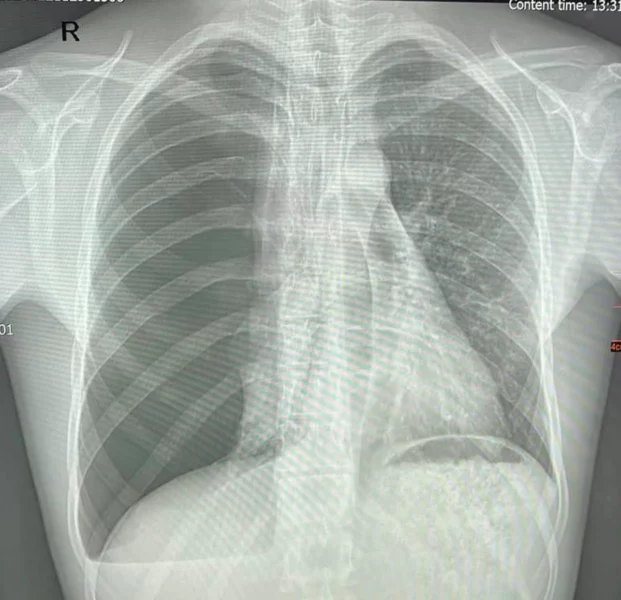

«Цього ж року, коли хлопець проходив плановий медогляд у Дрогобицькому ТЦК і його направили до «ОХМАТДИТу» для стаціонарного обстеження, оскільки побачили у Олександра шрам після операційного втручання. Під час діагностики наші лікарі виявили пневмоторакс. Давність захворювання невідома, адже скарг ніяких у хлопця не було роками. Фактично, Олександр дихав однією легенею невідому кількість часу»,- йдеться в повідомленні.

«Це загрозливий для життя стан. При такому діагнозі може бути летальний наслідок. При цьому хлопець не відчував жодних симптомів або не звертав увагу. Ми коли зробили знімок і побачили результат, то були шоковані», – наголосив торакальний хірург Центру Олександр Колодій.